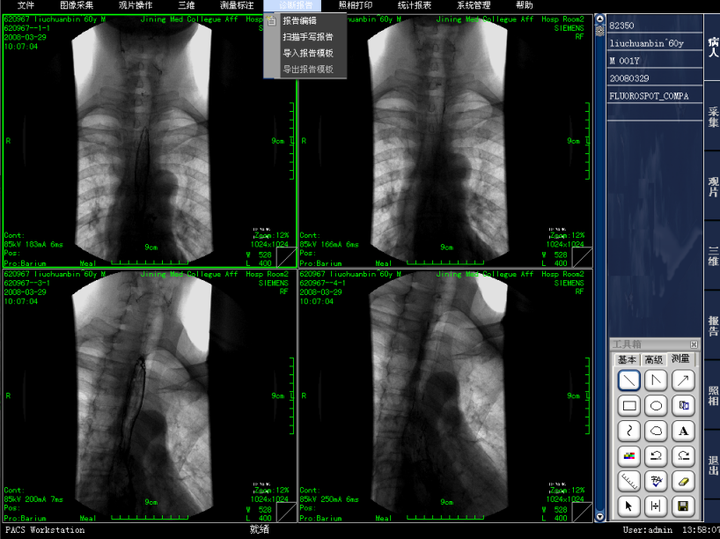

• 报告编辑

• 报告模板多样化

二维图像处理:支持图像无级缩放、图像旋转、翻转、图像移动漫游、图像黑白翻转、伪彩、放大镜、图像复制、窗宽、窗位调节、预设窗宽/窗位、ROI自动窗宽、窗位调节、窗宽、窗位曲线调节、显示双窗宽/窗位、测量、标记、距离测量、角度测量、椭圆测量、任意形状面积测量、文字注释、图形、箭头标注、可手画线、长度、面积计算显示、ROI平均密度值测量:圆形、矩形等、图像拼接、图像增强、心胸比测量;

2、影像诊断与分析:医生可以利用PACS系统进行影像的放大、旋转、对比度调节等操作,以获得更清晰的诊断结果。

3、临床诊断:医生可以通过PACS系统查看和分析患者的影像,辅助诊断疾病。